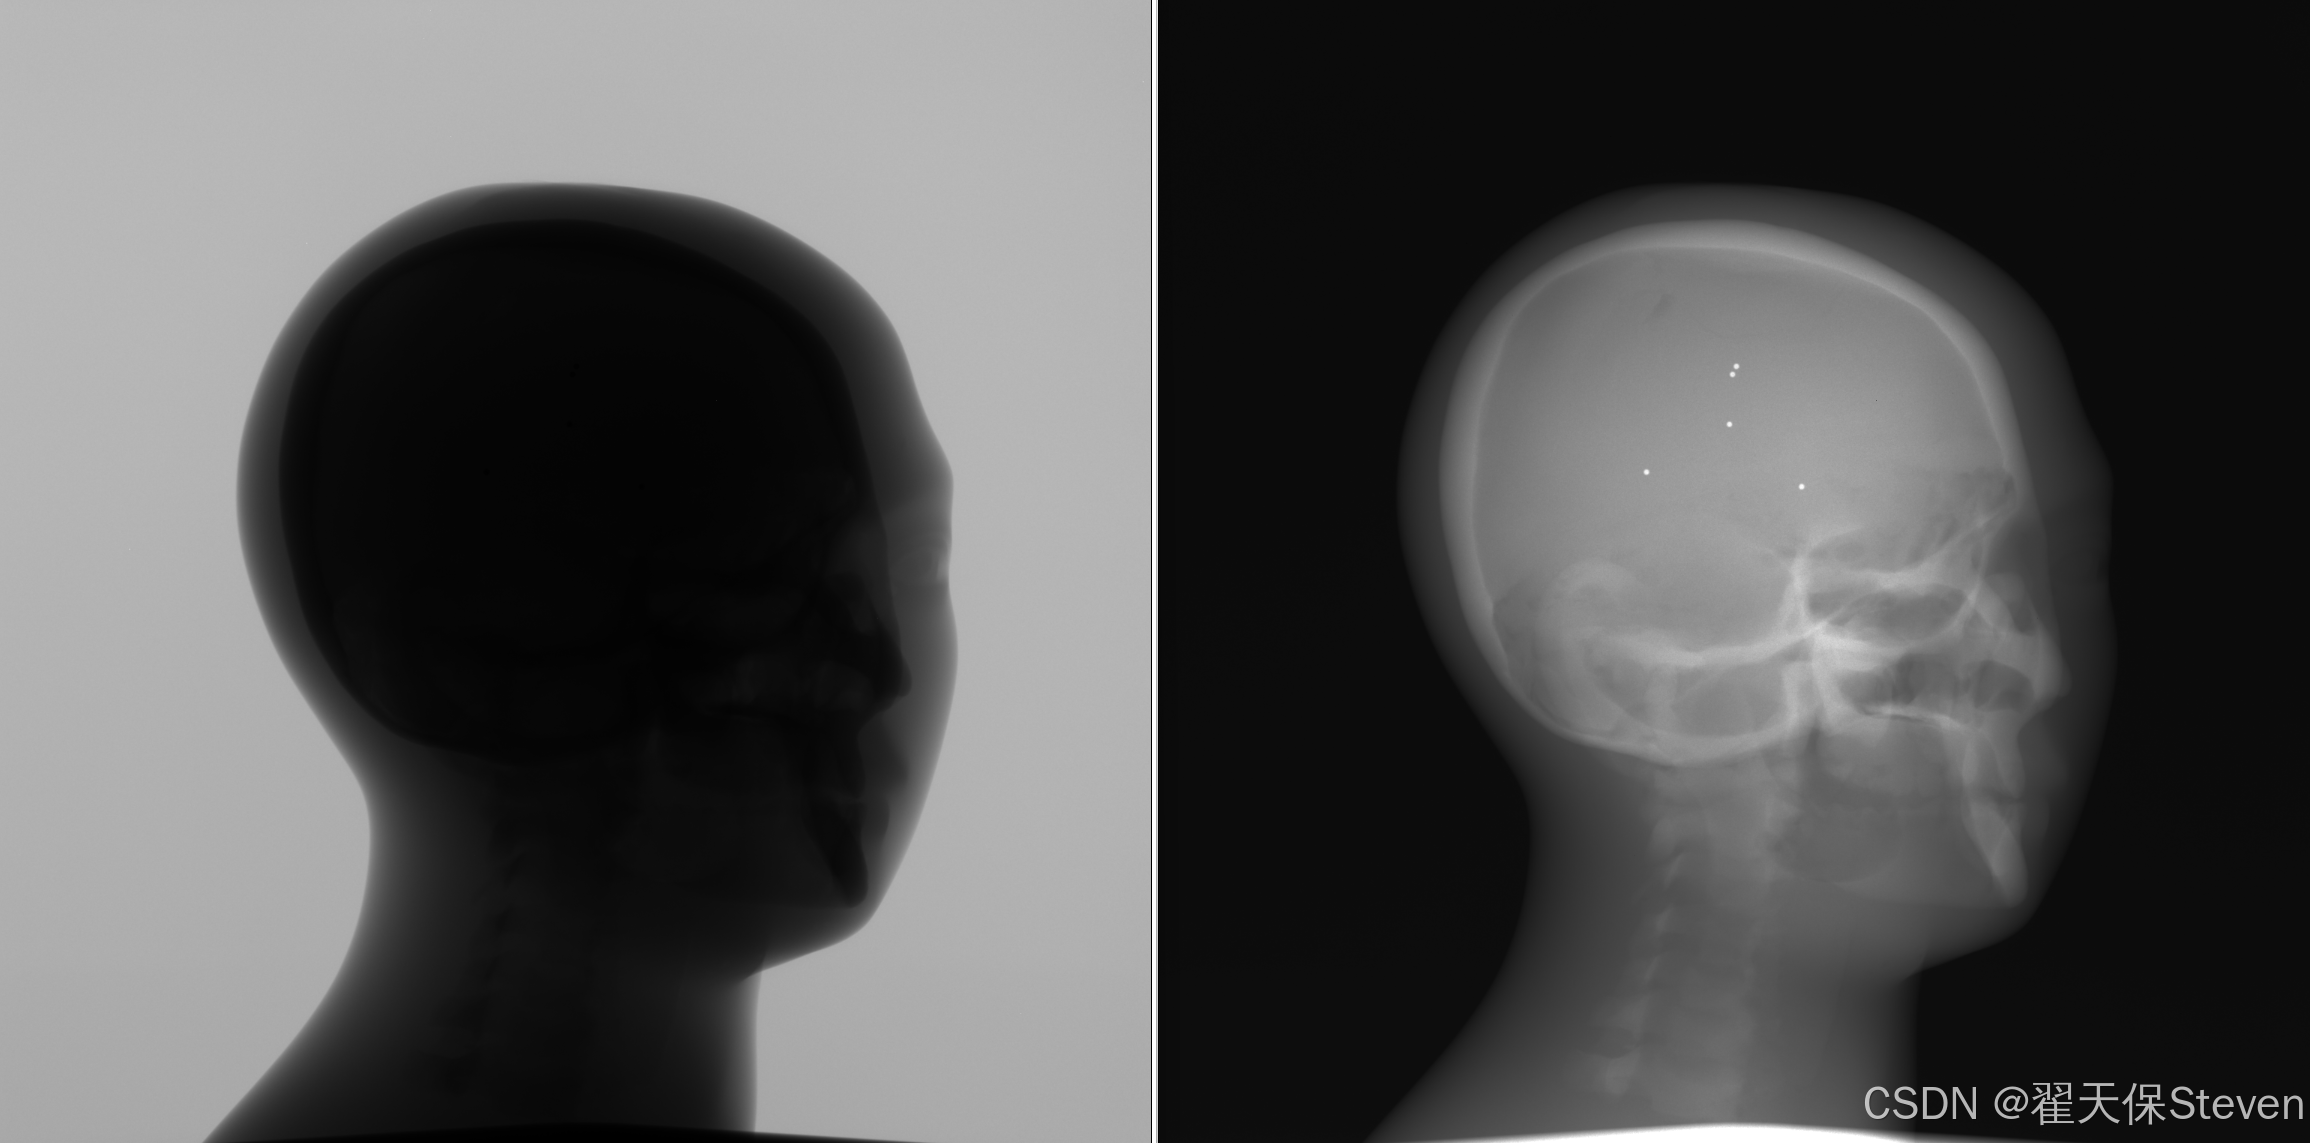

3.1 X光图像采集

采集装置由微焦点X射线源、单轴旋转台与二维平板探测器组成。被检测物体固定于旋转台上,X射线源与探测器同步围绕旋转轴旋转,旋转角度范围为[0, 2π]。在每个投影角度β下,探测器采集一幅二维投影图像,按空间几何比例关系映射至虚拟探测器,得到原始投影数据集,其中(β, a, b)分别对应投影角度、虚拟探测器水平坐标与垂直坐标。

该步骤的核心是获取X射线穿过物体后的强度分布,其物理过程遵循朗伯-比尔(Beer-Lambert)定律:X射线强度随穿过物质的厚度与密度乘积呈指数衰减,为后续密度重建提供原始物理信号。采集图如下: